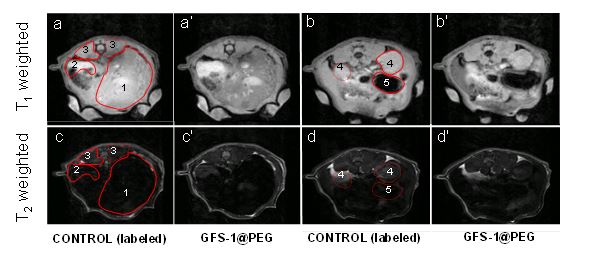

Desarrollan nanopartículas que mejoran el contraste en imágenes de resonancia magnética y facilitan el diagnóstico clínico